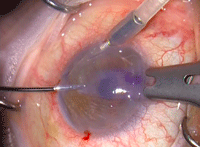

Figura 5. Inserción en la cámara anterior mediante técnica de pull-through. Con la pinza de Tan se tira del tejido desde una paracentesis contralateral.